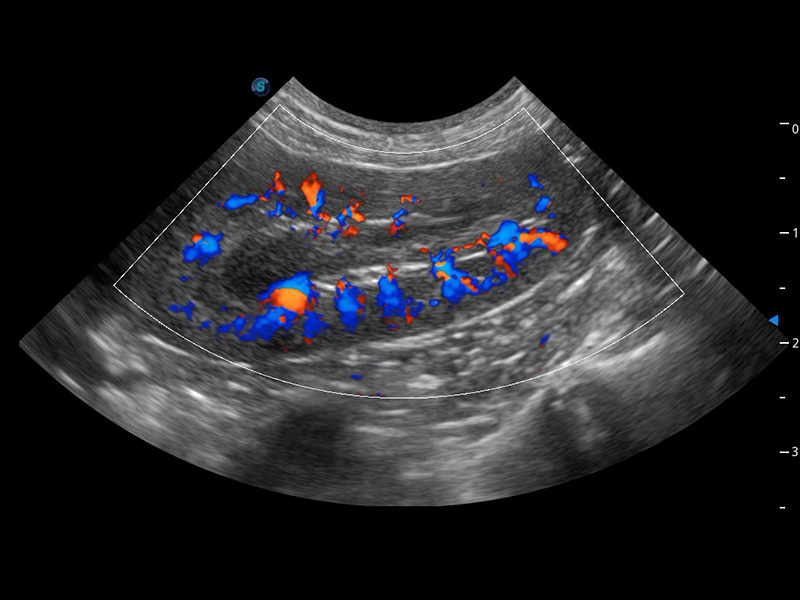

ProPet 60 作为一款高端台式动物超声设备,为动物医生的日常诊断提供了一系列贴合动物临床需求、解决临床实际问题的高级成像功能。凭借全系列高清探头,满足医生对腹部、心脏、生殖、浅表、肌骨等成像的所有需求,切实帮助您提升检查效率,提高诊断信心。

兽用彩色多普勒超声诊断系统

动物是人类最亲密的朋友和最值得信赖的伙伴。竞技宝(JJB)官方网站也一直致力于探索动物专用的超声影像解决方案。 全新推出的ProPet系列,是竞技宝(JJB)官方网站在动物超声影像智能化、专业化、精准化的一次跨越式革新。动物不能用言语来表述自己的不适,通过超声影像,ProPet系列搭建了动物医生与不同物种沟通的“桥梁”,为动物医生注入了“治愈之力”。